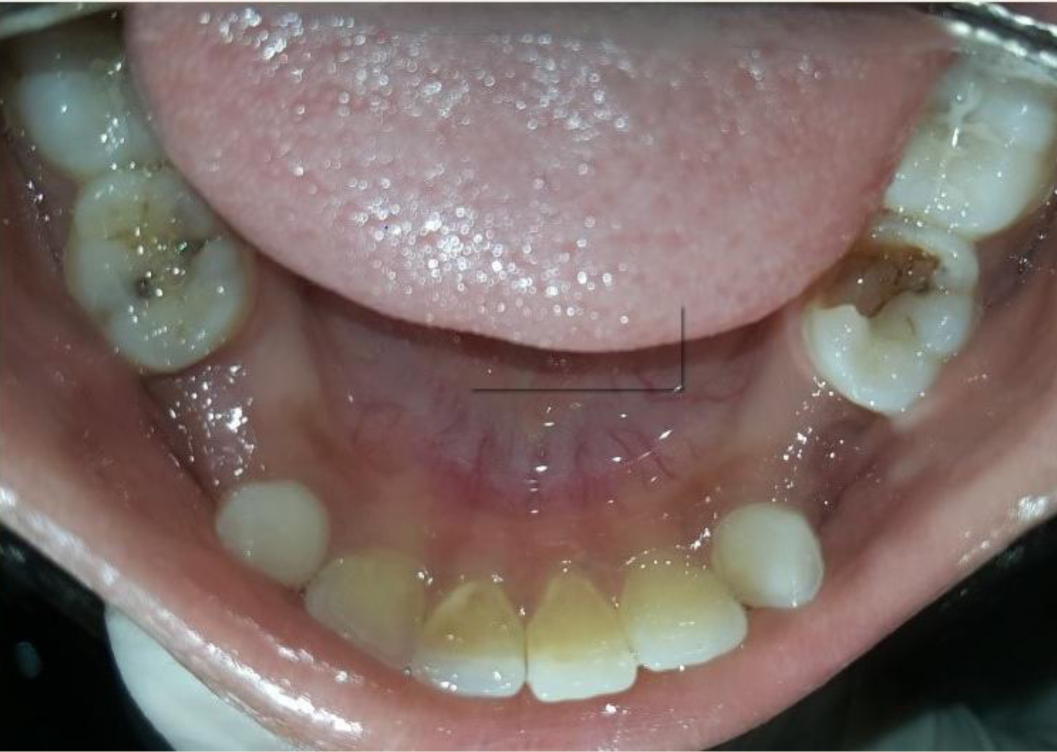

A nine year old boy reported to the Department of Pedodontics and Preventive Dentistry of Bharati Vidyapeeth Deemed University, Sangli with a chief complaint of pain and abscess in the lower left back region of the jaw since one month. Patient was a known case of autism spectrum disorder. He was inattentive, hyperactive and showed repetition of gestures. Psychological testing report showed childhood autism rating scale (CARS) 2, which falls into mild to moderate autistic category. Vineland social maturity scale (VSMS) measuring the social intelligence of child was found to be 31.5 with social age of around 5-6years. The family history was non-contributory. He was not on any medications and had reported no history of drug allergies. Extra-oral examination showed no specific findings (Figure 1). Intraoral examination revealed multiple carious lesions (Figure 2) (Figure 3). Occlusal caries involving enamel, dentin and pulp with 55 and 75. Intra oral dentoalveolar abscess was also seen in relation with 75 (Figure 4). Dentinal caries was seen with 85 and occlusal pit and fissure caries was seen with 65. No soft tissue abnormalities were appreciated. Radiographic evaluation by orthopantomogram was also done which revealed no abnormality (Figure 5). It was difficult for the patient to co-operate on the dental chair and understand the instructions given to him; hence treatment was planned under general anaesthesia. A complete pre anaesthetic evaluation was done and the patient was categorized under ASA II. Treatment plan was explained to the child’s parents and a written consent was obtained from them. The dental treatment done under general anaesthesia included pulpectomy of 55, 75 with glass ionomer cement restoration followed by placement of pre trimmed and pre contoured stainless steel crowns (Figure 6) (Figure 7). Glass ionomer cement restorations were done in 65 and 85 and pit and fissure sealants application on 16, 26, 36 and 46. Post-operative orthopantomogram showed well placed restorations and crowns (Figure 8). Patient’s post-operative recovery was uneventful. Treatment rendered reduced the pain and discomfort.Oral hygiene care instructions were given to the parents and maintenance protocol was explained and they were also encouraged for regular follow-up for preventive dental care. The two months follow-up revealed improved eating habits of the child.

Figure 3 Intra oral pre-operative image of the mandible.